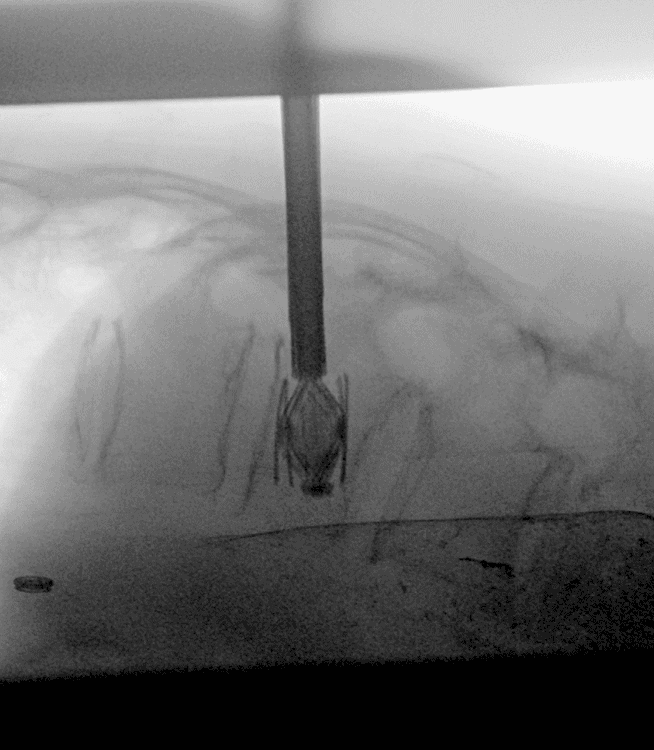

L'implant SPINEJACK vise à réduire la fracture in situ par restauration de la hauteur anatomique du corps vertébral.

Technique de traitement des fractures vertébrales ostéoporotiques